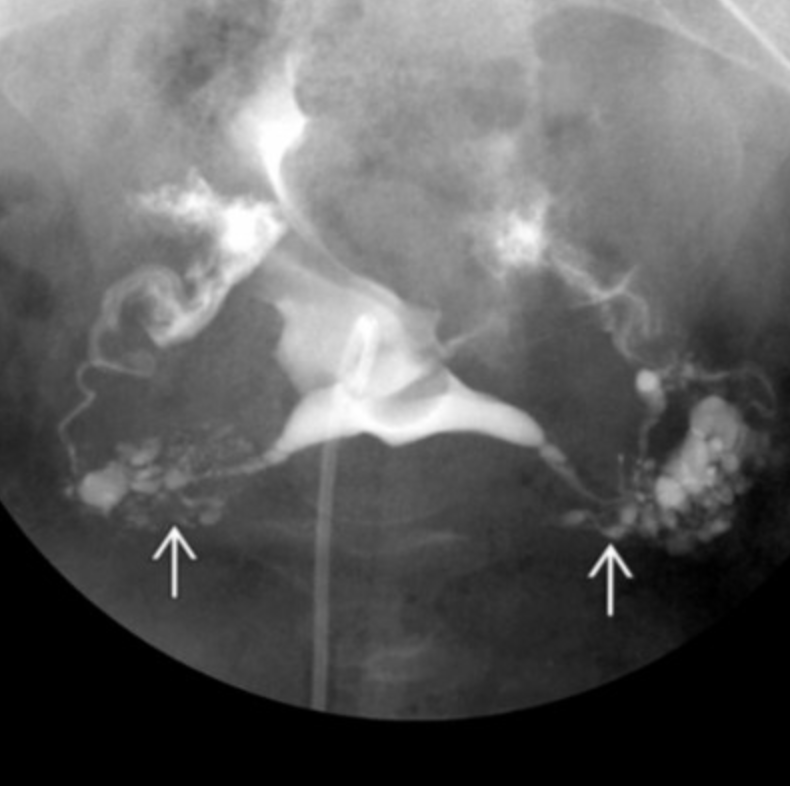

Salpingitis isthmica nodosa

• Basically nodularity/diverticula of the fallopian tubes

• Risk for ectopic pregnancy